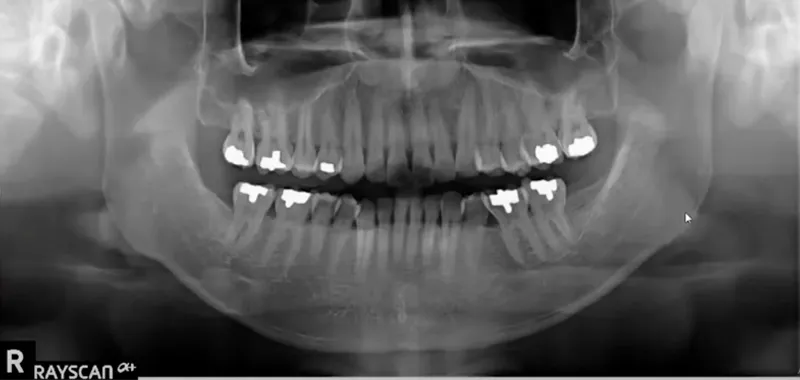

Enabling more accurate diagnosis and treatment, our CBCT (Cone Beam CT) scan captures detailed 3D images of your teeth, jawbone, nerves, sinuses, and surrounding structures—all in a single scan. Unlike traditional two-dimensional X-rays, CBCT technology provides a complete three-dimensional view from every angle, allowing us to see more, plan better, and treat with greater precision.

Hidden issues like root fractures, impacted teeth, bone loss, and infections become clearly visible with CBCT technology. This level of detail supports more accurate diagnosis and is especially useful when planning dental implants, extractions, orthodontic treatments, and root canals.